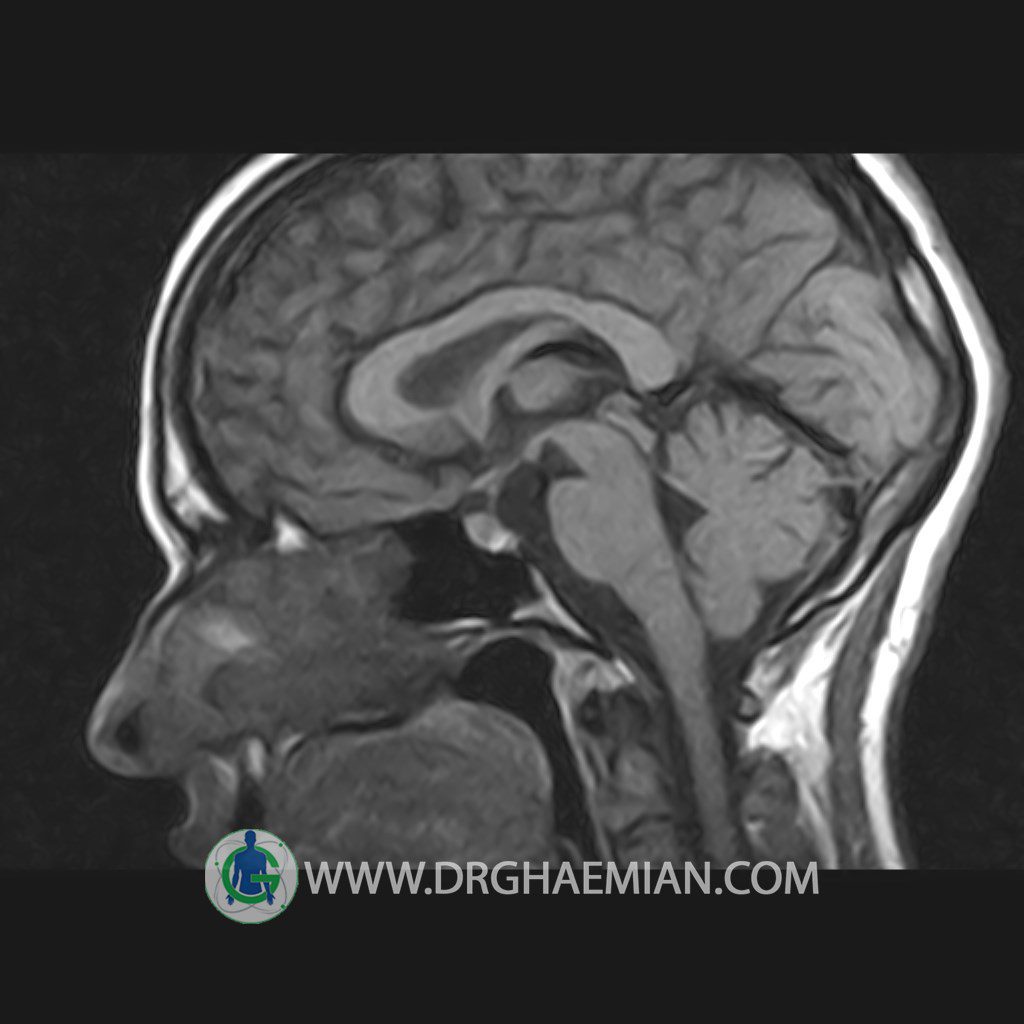

پزشکان اغلب از تصویربرداری ام آر آی برای تشخیص و درمان عارضه های پزشکی که فقط با استفاده از اشعه ایکس یا میدان مغناطیسی و امواج رادیویی قابل مشاهده است، استفاده می کنند. دستگاه ام آر آی تصاویر دقیق از ساختار های داخلی بدن ایجاد می کند. در این کیس هیپرپلازی هیپوفیز و آدنوم مشاهده می شود.

HYPOPHYSIS MRI

(with and without contrast)

Technique: Axial , coronal T1 , Axial , coronal , sagittal T2 , Axial, coronal T1 post Gd & 64 dynamic thin coronal slices.

REPORT :

The sella shows normal size , position and configuration .

The borders of its floor and walls are smooth and sharply defined .

The infundibulum is centered and of normal size .

The optic chiasm and suprasellar spaces appear normal .

The cavernous sinus and imaged portions of the internal carotid artery and carotid siphon are unremarkable .

Evaluable portions of the neurocranium show no abnormalities .

The sphenoid sinus is clear and pneumatized .

– Mild convexity at superior border of pituitary gland with post contrast homogeneous enhancement suggestive for pituitary hyperplasia & iso signal adenoma

is seen